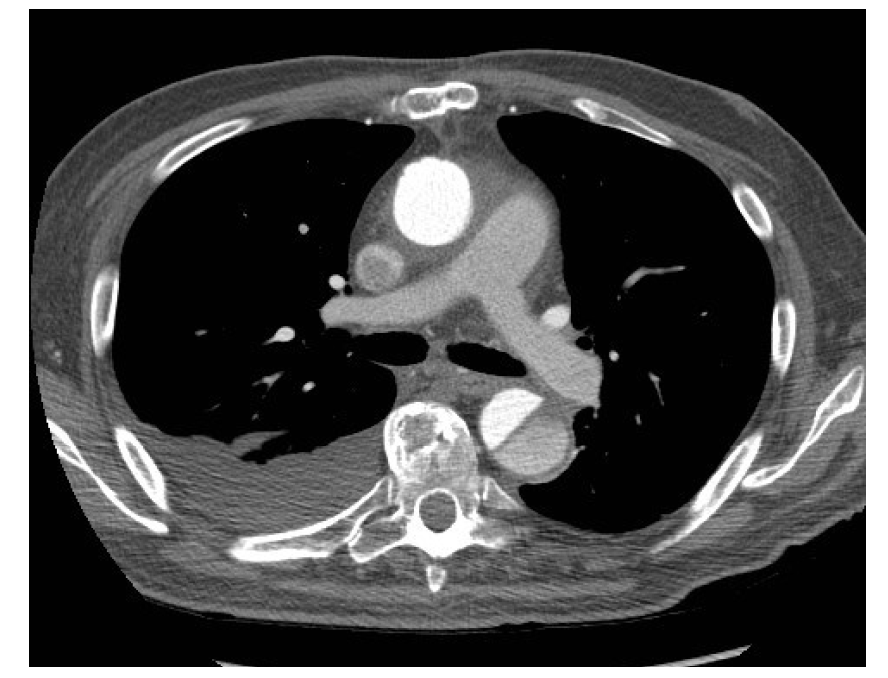

What is this?

IMH